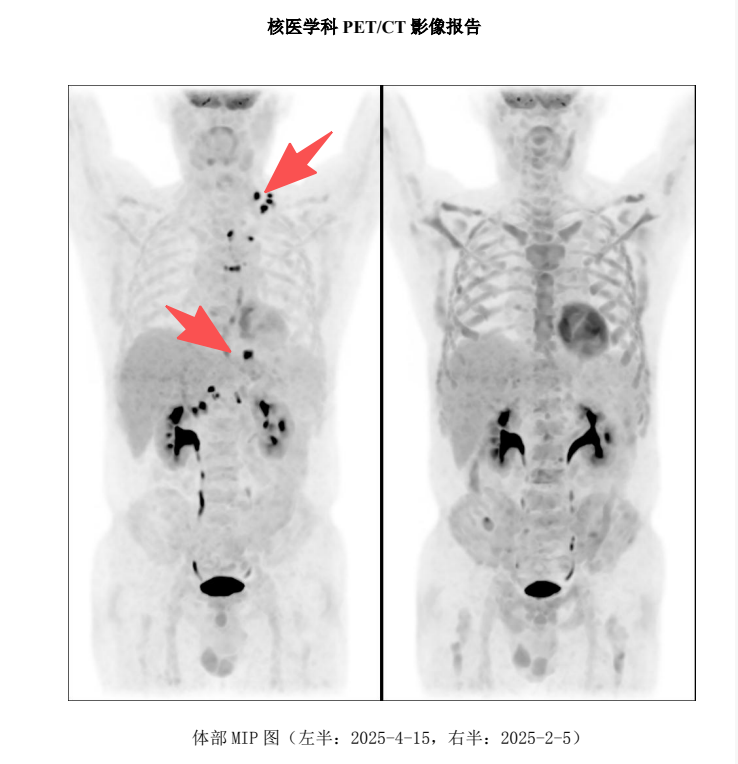

25年5月底进仓,6月初陆续回输了半相合的儿子干细胞以及脐带血细胞,6.25出仓,PET-CT评估,完全缓解!

26727c097af6ae8b6bb0027b0cbb11fc.png